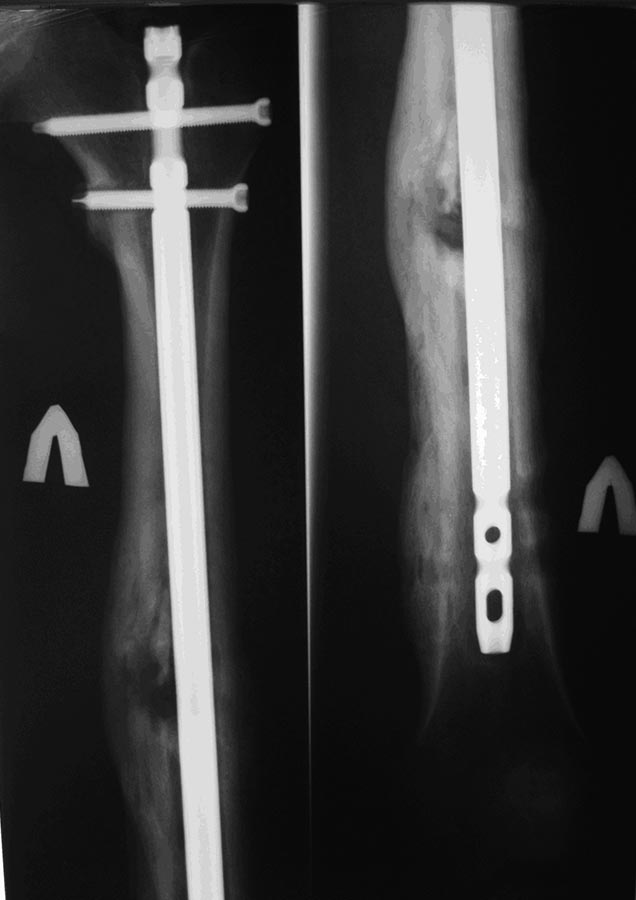

Уважаемые коллеги, представляют на обсуждение клинический случай!Пациент 26 лет, около года назад получил травму в результате ДТП. По поводу перелома диафиза бедренной кости выполнялся БИОС.

Спустя 4-5 мес. пациент обратился с болями в нижней трети бедра (проекция дистальных блок. винтов). При RG выявлена их миграция, выполнено их удаление.

Спустя еще 4-5 мес обратился с жалобами на припухлость в области дистального блокирования. В поликлинике сделали снимки и, с подозрением на остеомиелит, оправили в стационар.

Снимки представлены.